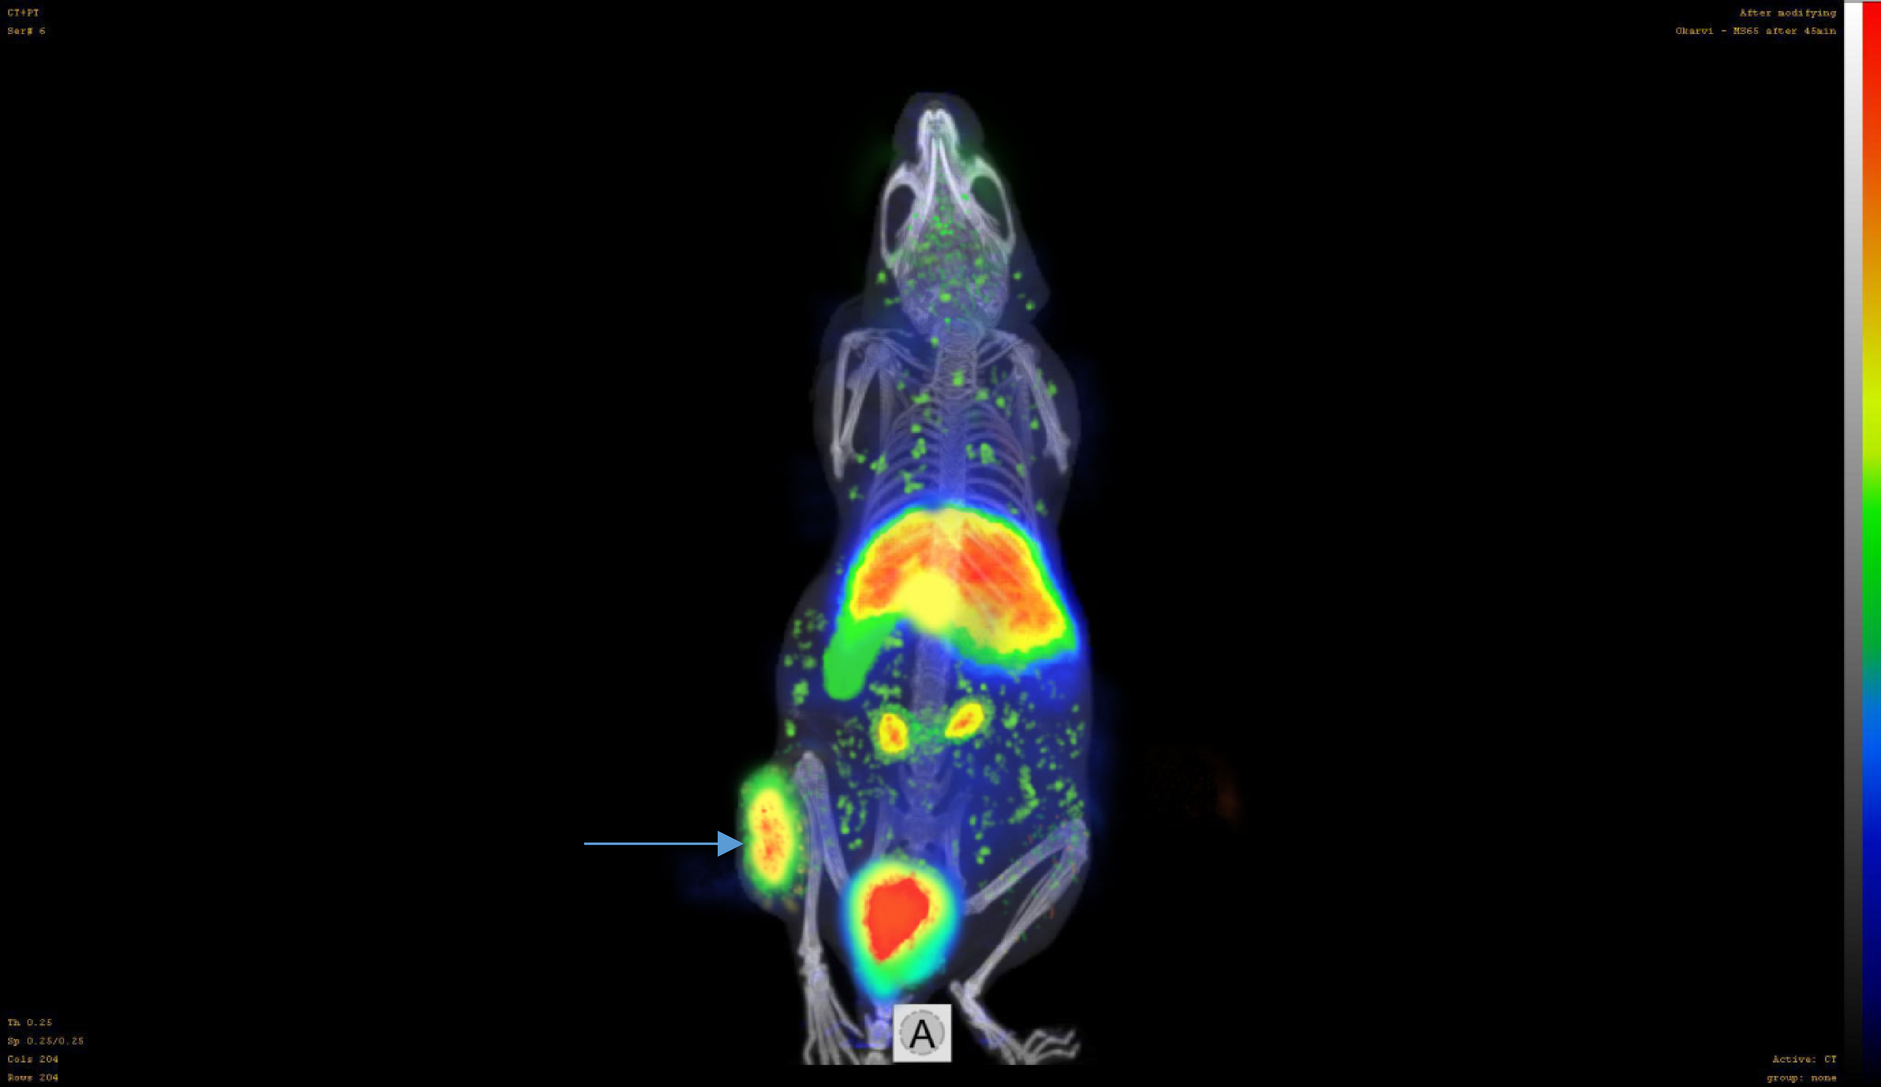

Fig. 7

Micro-PET camera image of a female nude mouse model with ER-positive MCF-7 tumor xenografts at 45 min post intravenous tail injection of 150 µCi of the [68Ga]-DOTA-estradiol. High abdominal activity can be seen in the image. The arrow indicates the tumor location.